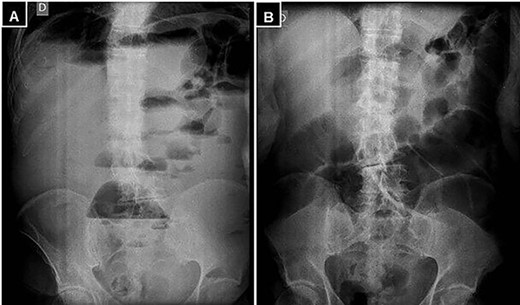

A supine and upright plain X-ray of the abdomen were obtained and showed dilated small bowel loops, mainly in the left upper abdomen, along with multiple air-fluid levels (Fig. 1). Computed tomography (CT) demonstrated significant air-fluid distention of the entire small bowel, up to the right flank and periumbilical region, where a change in caliber was observed (Fig. 2). The findings corresponded to small bowel obstruction (Fig. 3).

(A) Standing abdominal X-ray, and (B) supine position demonstrating marked distention of the small intestine and multiple air-fluid levels.